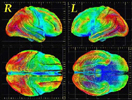

Η αύξηση του μέσου όρου ζωής στις αναπτυγμένες και κυρίως, στις υπό ανάπτυξη χώρες, έχει ως αποτέλεσμα και την αύξη ση της συχνότητας εμφάνισης των παθήσεων της τρίτης ηλικίας, όπως η υπέρταση, η στεφανιαία νόσος, τα αγγειακά εγκεφαλικά επεισόδια και οι άνοιες.